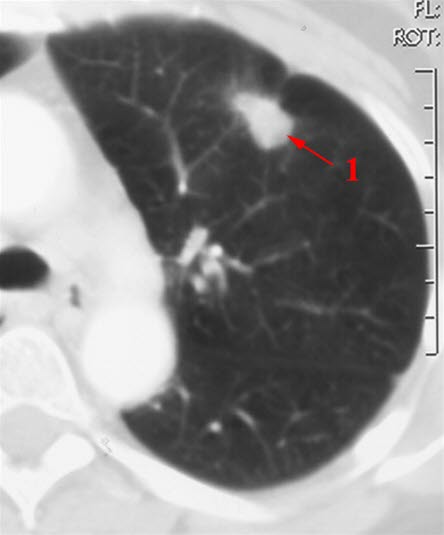

CT-bilde av lunge med svulstLungekreft er den kreftformen som tar flest liv i Norge, og den utgjør rundt en av ti nye krefttilfeller. Lungekreft omfatter alle kreftformer i lunger og/eller luftveier (bronkier). Omtrent 90 prosent av alle tilfeller av lungekreft er bronkialkreft. Andelen pasienter med spredning på diagnosetidspunktet er mellom 40 og 50 prosent.